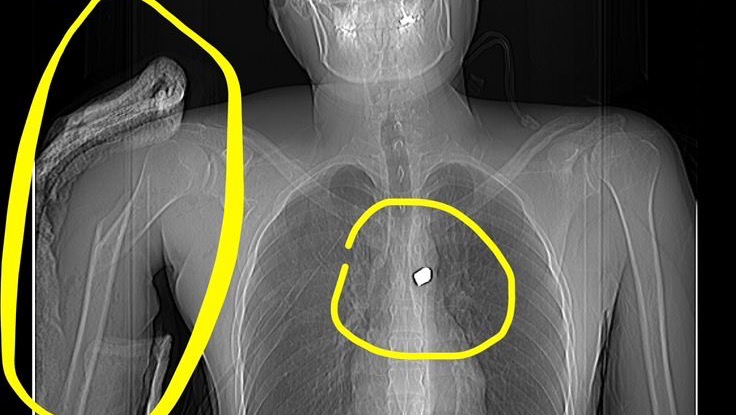

Fue víctima de un asalto a mano armada, el cual, el asaltante le disparó a quemaropa. Impactando en brazo, destrozando hueso, afectando pulmón, hasta llegar a la medula Ósea, causándole daño irreversible.